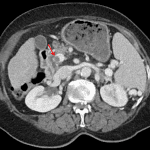

Indication: Right upper quadrant pain, history of ablated HCC

- Nonocclusive thrombus in the main portal vein

- Hypodense ablation zone in segments 7/8 without associated nodular enhancement

- Cirrhotic liver morphology

- Splenomegaly

- Multiple upper abdominal venous collaterals including esophageal varices and a large splenorenal shunt

- Portal vein thrombosis

Nonocclusive thrombus in the main portal vein.

Hepatic cirrhosis with stigmata of portal hypertension including esophageal and upper abdominal varices and splenomegaly.

Ablation zone in the right hepatic lobe without associated nodular enhancement to suggest residual/recurrent disease.